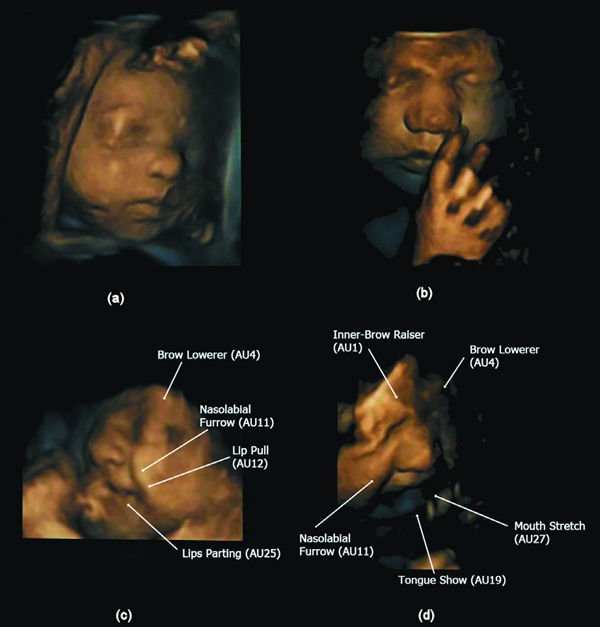

Figure 2. Illustration of neutral faces over gestational age and combinations of action units (AUs) for the laughter and cry gestalts. (a) neutral face at 28 weeks and (b) at 33 weeks. (c) 4 AUs contributing to the laughter gestalt at 32.5 weeks and d) 5 AUs contributing to the cry gestalt at 33 weeks. doi:10.1371/journal.pone.0024081.g002

The scans were made in the second and third trimester. The researchers found that between 24 and 35 weeks, the occurrence of 3 or more facial movements increased from 7-69%. Also, recognizable facial movements were discernible, rising from 0% to 42%. This led to specific facial expressions increasing from 0-35%. The frequency with which the changes occurred also increased with age.

The present study confirms that over the second to third trimester fetuses develop a large amount of facial action units producing movements that near emotional expressions including those found in the cry and laugh face.

The complexity of the movements also increased over time.